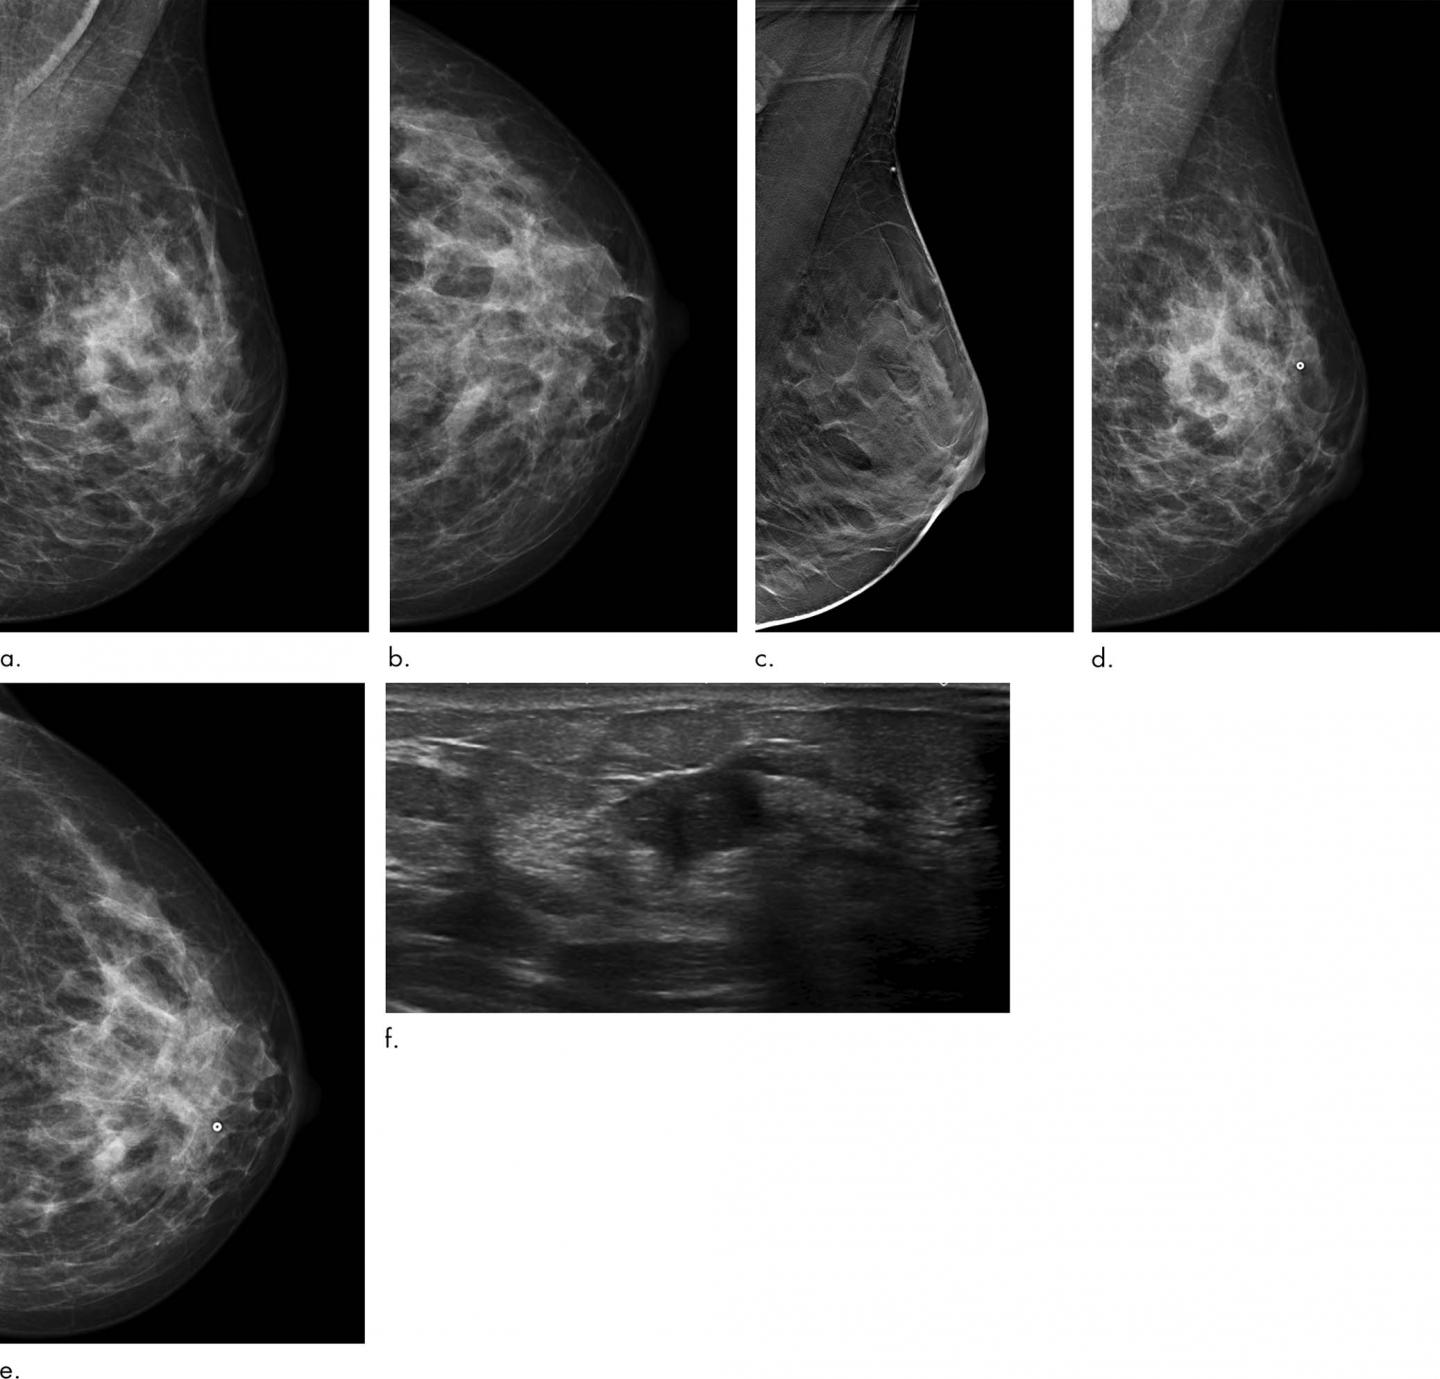

OAK BROOK, Ill. - Screening with digital breast tomosynthesis (DBT) reduces the rate of interval breast cancers compared to screening with digital mammography, according to a study published in Radiology . The study adds to a growing body of evidence supporting DBT as a breast cancer screening tool with important advantages over mammography.

DBT works by capturing a series of X-ray images of the breast from different angles. Previous research has shown that it has a higher sensitivity for breast cancer detection than digital mammography.